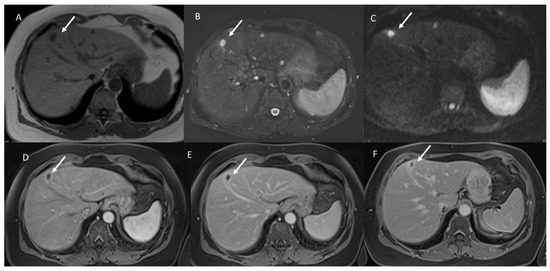

- The signal intensity (SI) in T1 W, in T2-W, DWI sequences and the apparent diffusion coefficient (ADC) map.

3.2. T2-W Signal Intensity and Diffusion

3.3. Arterial Phase Appearance

3.4. Portal Phase Appearance

3.5. Equilibrium Phase Appearance